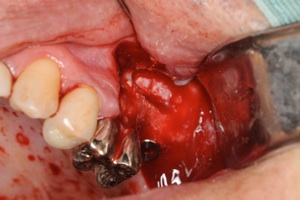

サイナスリフトをしている様子、横から骨を取り、上顎洞の粘膜を剥離していきます

粘膜が薄かったことが原因で粘膜が破れてしまい、サイナスリフトは中止、ここで

無理をしてオペをしてもいいことはないので、中止の勇断も必要です